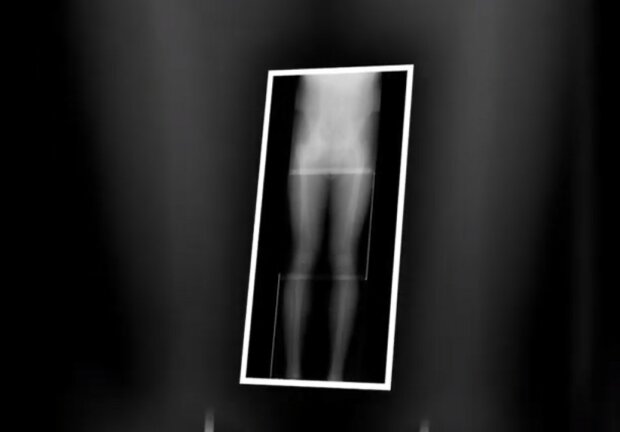

Prodloužení končetin se provádí takto: pacient dostane anestezii a zlomí mu nohu na dvou místech.

Chirurgové dělají na stehně 4-6 malých řezů. Poté jsou kosti umístěny v chrupavce teleskopické tyče.

Teleskopické zařízení se pak postupně posouvá - rychlostí milimetru za den. Dva segmenty kosti se od sebe postupně oddělují, nová kost vyplňuje mezeru, svaly a šlachy se protahují.